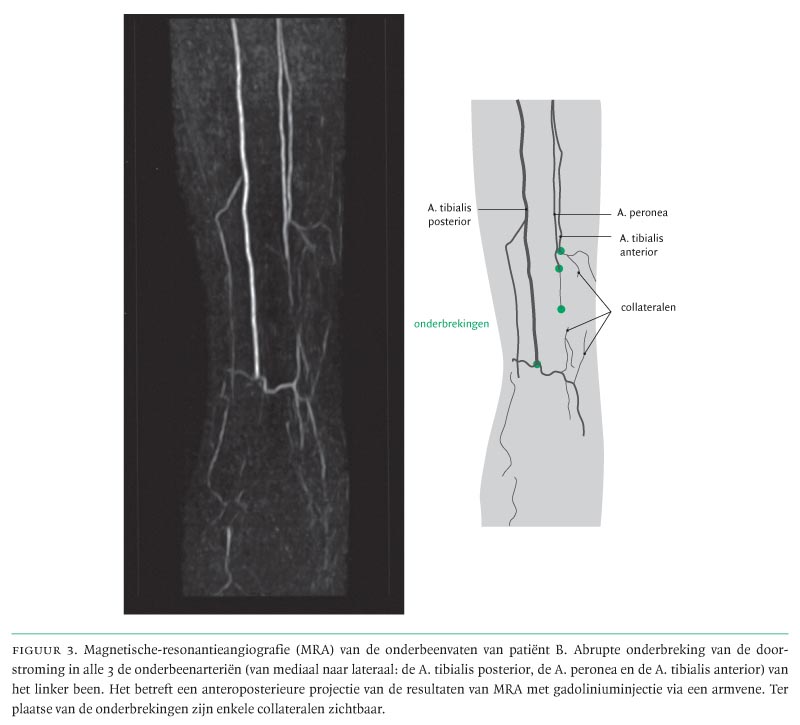

Laboratoriumonderzoek toonde, behoudens een verhoogde bezinking van 115 mm/1e uur (9/l, geen afwijkingen, met name geen stollingsafwijkingen, nierfunctiestoornissen of immuunpathologische afwijkingen. Bij echocardiografie en cardiale MRI werden geen afwijkingen gevonden, met name geen aanwijzingen voor een emboliebron. Ook de CT-scan van het abdomen liet geen afwijkingen zien. Bij MRA van buik- en beenvaten werd een afsluiting van de A. tibialis anterior en de A. tibialis posterior gezien (figuur 3) en trombusvorming met een vaatwandreactie die paste bij vasculitis of thromboangiitis obliterans. Er werd een huidspierfasciebiopt genomen hoog uit de kuit. Deze locatie, buiten het gebied van ischemie, werd gekozen ter voorkoming van problemen bij de wondgenezing na biopsie. Het biopt liet geen aanwijzingen voor vasculitis zien. De diagnose luidde ‘thromboangiitis obliterans’. Patiënte werd dringend verzocht te stoppen met roken en orale anticonceptie werd gestaakt. Zij kreeg acenocoumarol en simvastatine. Verder werd het ketanserinegebruik gestaakt en patiënte kreeg iloprost intraveneus gedurende 4 weken.8 Hierop trad een duidelijke klinische verbetering op aan de linker voet. Waar eerst gevreesd werd voor de noodzaak van een onderbeenamputatie, bleef de schade beperkt tot autoamputatie van digiti IV en V. In verband hiermee werd een orthopedische schoen aangemeten. Sindsdien is patiënte in een klinisch stabiele, goede toestand, nu ruim een jaar.